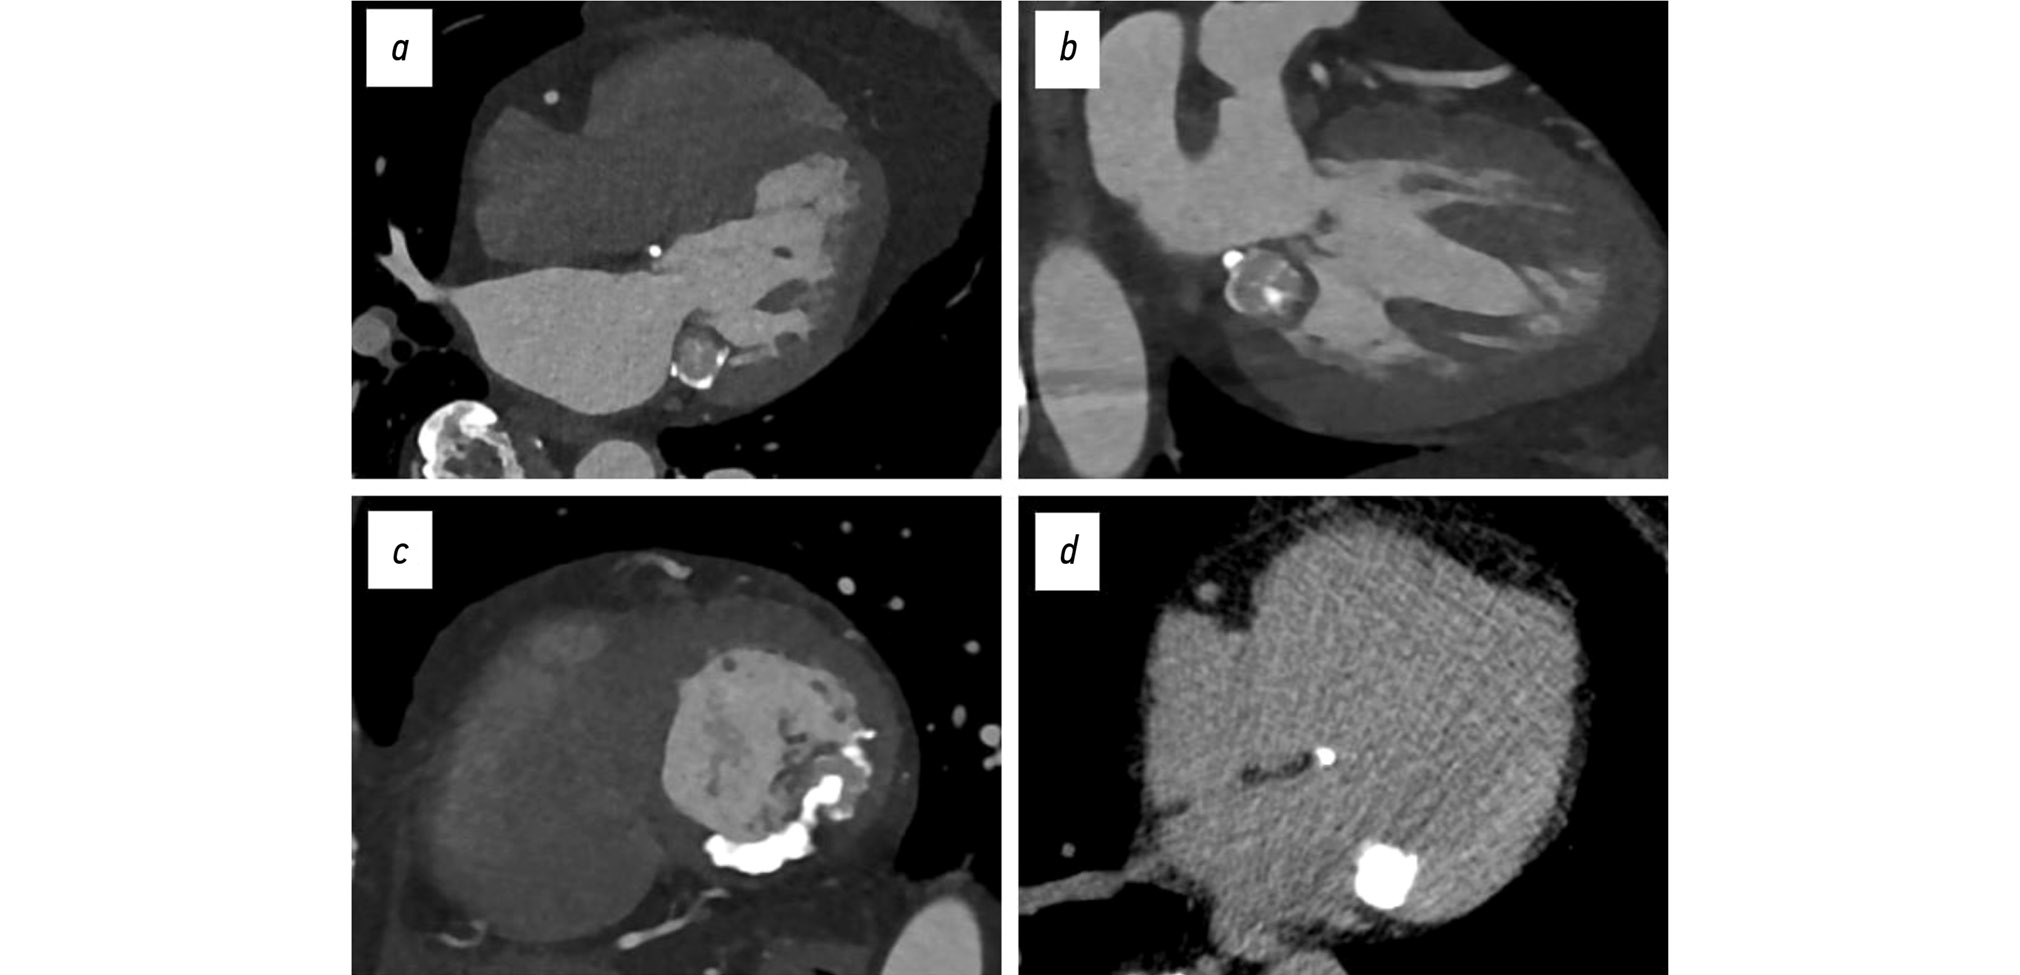

To further evaluate the lesion, ECG-gated cardiac CT angiography was performed. The scan identified a rounded calcified lesion measuring 35 × 12 mm at the level of the mitral annulus in the subvalvular region of the left ventricle. The lesion appeared heterogeneous, with calcified areas showing densities of 1,300–1,350 HU and a central region of lower density (330–340 HU), with no contrast enhancement observed during either the arterial or venous phases. These characteristics were consistent with caseous subvalvular calcification of the mitral annulus (Fig. 3).

Fig. 3. ECG-gated cardiac computed tomography, clinical case 2: a–c, contrast-enhanced images, bone window; d, noncontrast image, soft tissue window; findings consistent with caseous subvalvular calcification of the posterior mitral leaflet: a, four-chamber view; b, two-chamber long-axis view; c, short-axis view at the mitral valve level; d, axial view.

Additional imaging using the bone window demonstrated a heterogeneous calcified area near the base of the posterior mitral leaflet, also measuring approximately 35 × 12 mm, with a density reaching up to 1,680 HU.